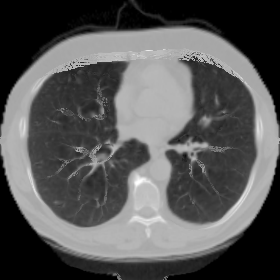

7.3. Real CT images

We now consider applying the proposed image registration method on real lung CT images retrieved from the National Lung Screening Trial (NLST) dataset [1]. Fig. 9(a) and Fig. 9(b) show two slices of lung CT images that we use as the source and the target (see Fig. 9(c) for the absolute intensity difference). We remark that the CT images are originally with different intensity, and so we apply an intensity histogram matching before running the registration experiment. Fig. 9(d) shows the registration result obtained by our proposed method. It can be observed that our method successfully produces a large deformation on the right lung of the source image to match that of the target image (see also Fig. 9(e) for the final absolute intensity difference). On the contrary, DDemons [47] (Fig. 9(f)), LDDMM [5] (Fig. 9(g)), Elastix [29] (Fig. 9(h)) and DROP [18] (Fig. 9(i)) all fail to produce an accurate and bijective registration result. This shows that our method is more capable of handling large deformation image registration.